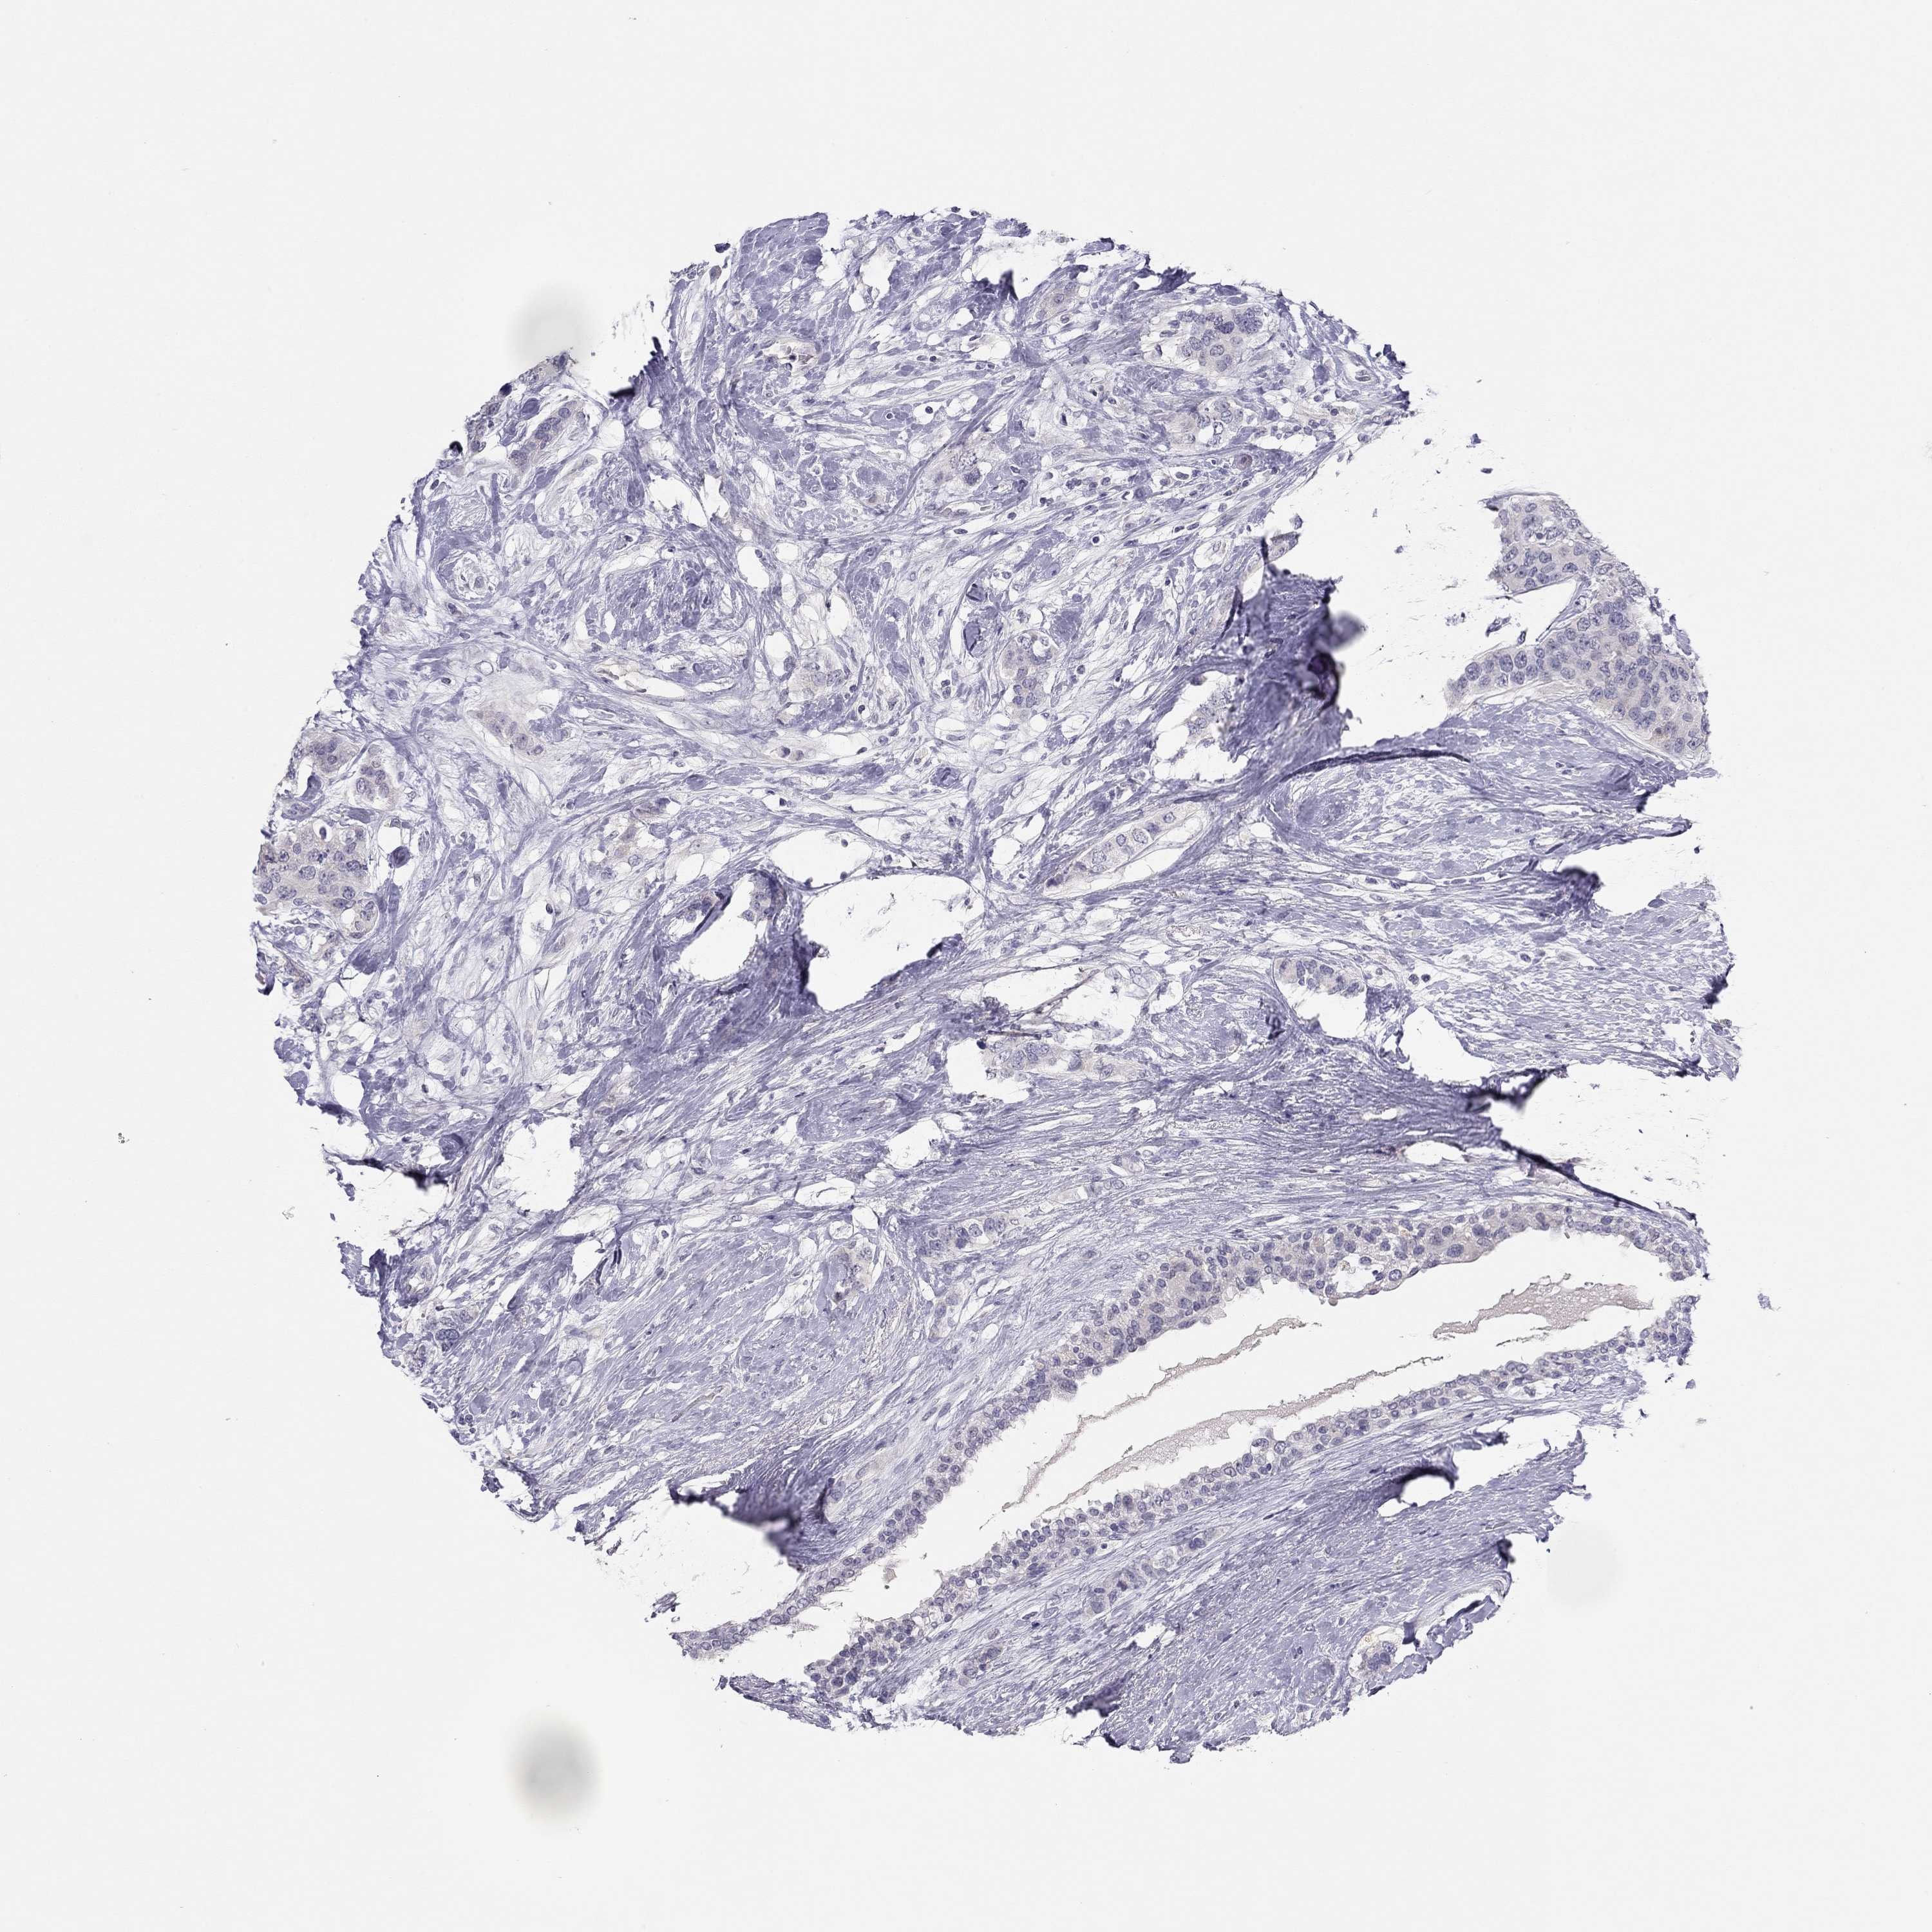

CANCER BREAST CANCER Show tissue menu

BRCA TCGA BRCA VALIDATION PROTEIN EXPRESSION